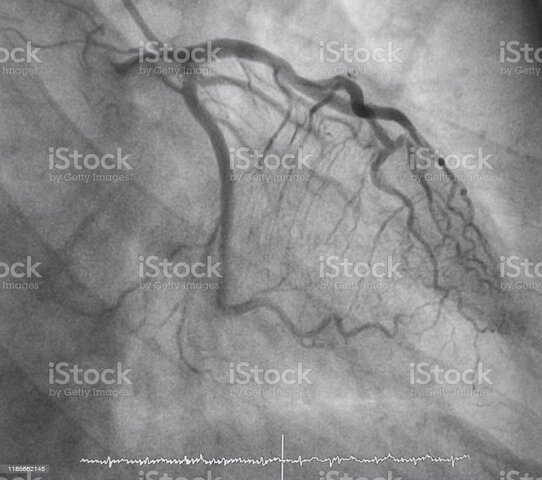

• Angiografía coronaria

Angiografía coronaria

Eduardo Pereira canalizo por primera vez la arteria radial para realizar una angiografía coronaria. Técnica de Seldinger en 1953 que permitía acceder a los vasos sanguíneos de forma mucho más seguro (Chen et al., 2014).